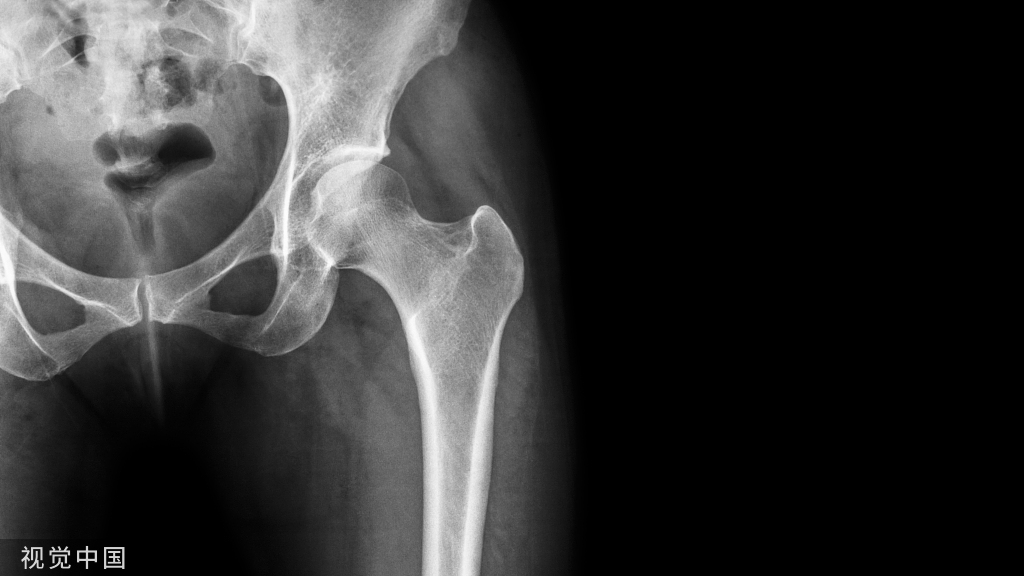

• X-ray阴性。(MRI不是阴性)

影像学

冈上肌出口位片或者肩胛骨Y位片可显示肩峰形态

影像学检查

MRI具有很高的诊断率(95%以上)

辅检:X线片(肩关节Y位片)MRI   (SIMENS 1.5T  Aera)